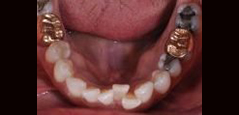

Lower teeth with crowding, a condition treatable with Invisalign.